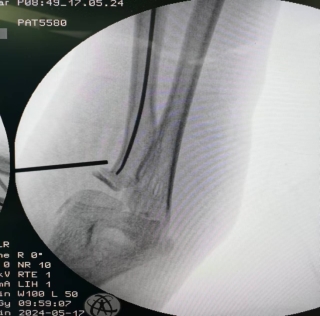

患儿,女,11岁,5月14日因“外伤后右肘肿痛1小时余”入院,术前X线提示右侧桡骨颈骨折,O’Brien分型Ⅱ型,入院后我科陈义权主任立即和张浩医生采用中医特色骨折夹板固定骨折处,于5月17日予右桡骨颈骨折闭合复位弹性髓内钉内固定术,术中我科陈义权主任采用Metaizeau技术,在腕部做一长约1cm切口,利用弹性髓内钉闭合复位骨折端。术后3月复查,骨折端基本愈合。我科成功将中医特色治疗与小儿骨折微创治疗技术完美结合。

图3、4:术中透视下X线